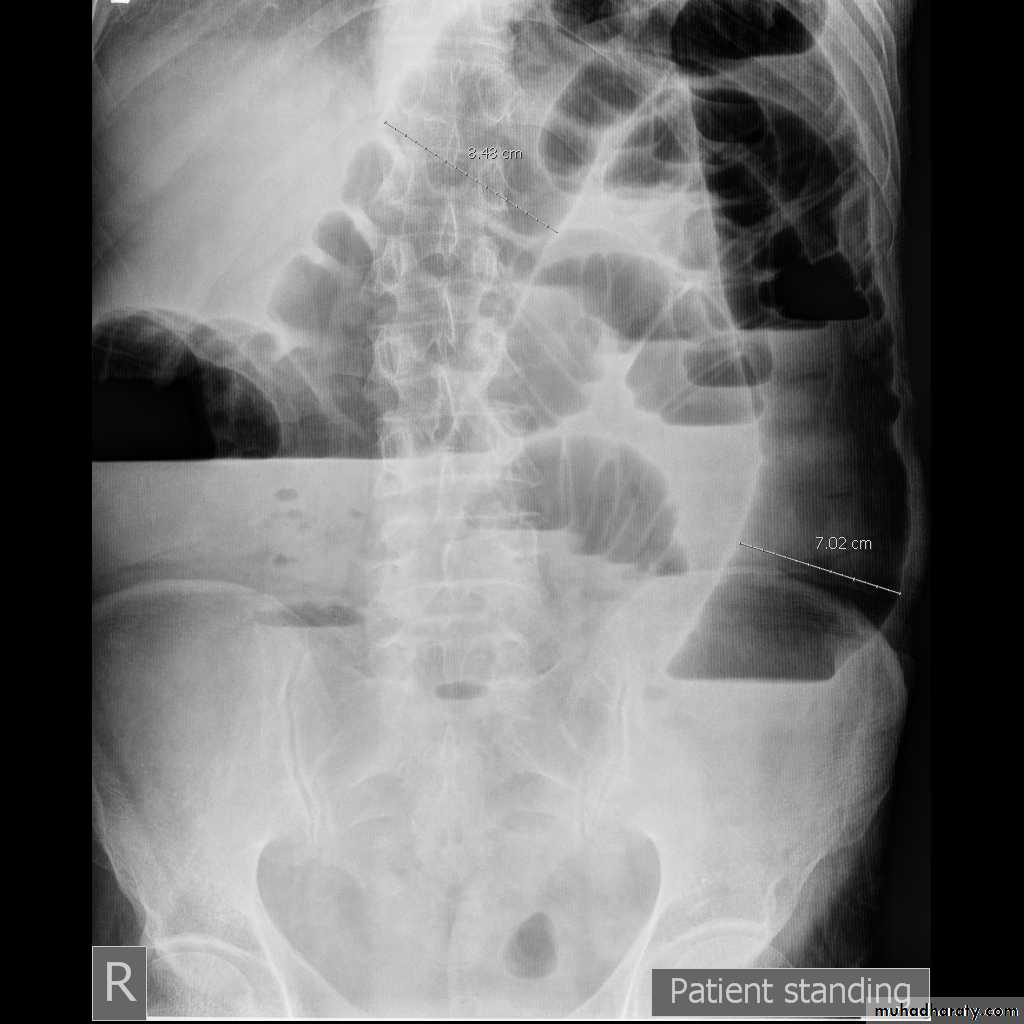

- upright films: dilated small bowel loops (>3 cm in diameter), air-fluid levels, and a paucity of air in the colon.

Small bowel obstruction

-The dilated bowel loops centrally located and lie transversely.-No/minimal gas is seen in the colon.

-valvulae conniventes,which completely pass across the width of the bowel

-ladder pattern

Multiple air fluid level, small and centrally located.